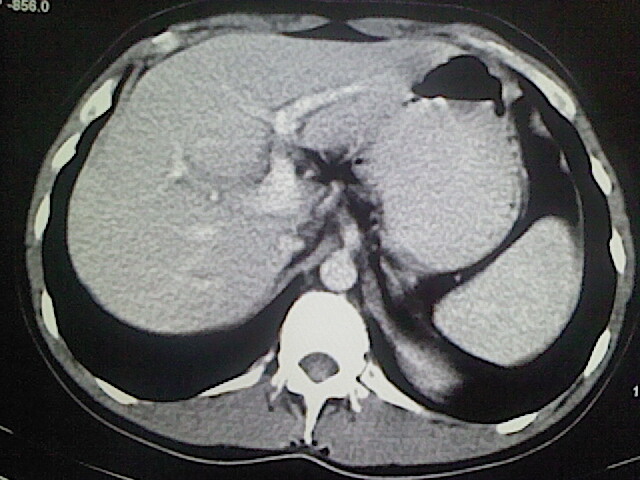

以下是引用卜一在2009-3-14 9:49:00的发言:[br]胆囊萎缩,胆囊壁不规则增厚,内部结构模糊,增强明显强化。另:肝左叶外侧段肝囊肿。支持:慢性胆囊炎!高度可疑:胆囊癌!

以下是引用余辉在2009-3-14 8:48:00的发言:[br]1)慢性胆囊炎。2)肝左叶外侧段肝囊肿。3)脂肪肝。[br]支持,胆囊萎缩,密度增高,不知b超具体有何提示,钙胆汁?结石?

以下是引用jiangjing在2009-3-14 10:18:00的发言:[br]1)慢性胆囊炎。2)肝左叶外侧段肝囊肿。3)脂肪肝。4.】建议行肝功能检查